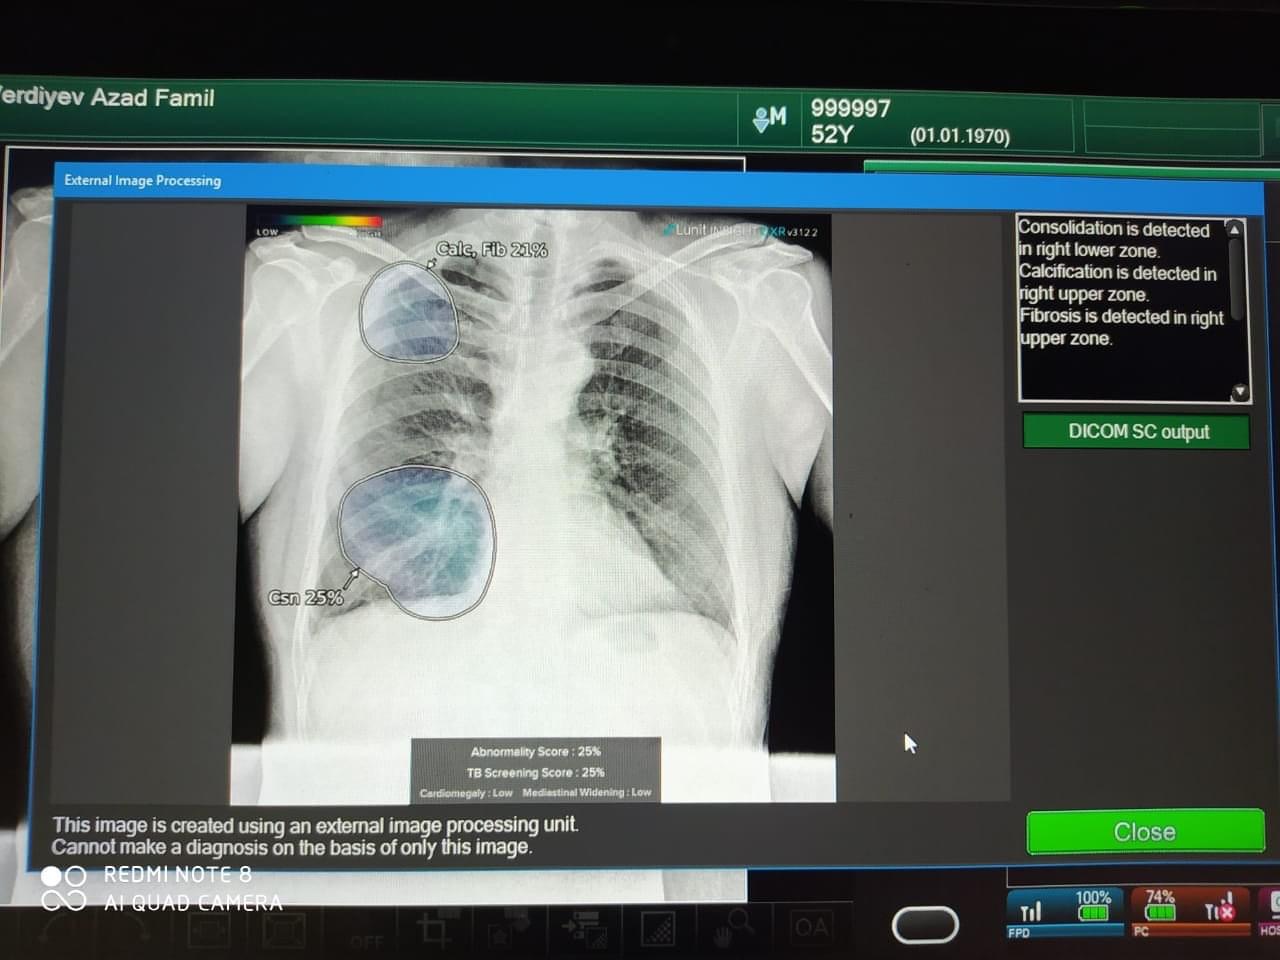

Sağlamlığa Xidmət İctimai Birliyi Azərbaycan Vərəm Əleyhinə QHT Koalisiyasının əməkdaşları ilə birgə "Qazilərə hörmət, evində xidmət" şüarı altında ağciyərlərin rentgen müayinəsi aksiyasına start verib.

Aksiyada 20-dən çox qazi və şəhid ailəsi üçün öz evində pulsuz Yapon istehsalı olan ən müasir portativ FDR X-Air adlı süni intelektə malik Rentgen aparatı ilə ağciyərlərin müayinəsi həyata keçirilib. Müayinə olunanlardan 2 nəfərin ağciyərində patologiya aşkar edilib. Həmin şəxslərə gecikdirmədən əlavə müayinə və müalicə üçün həkimə müraciət etmələri məsləhət görülüb.